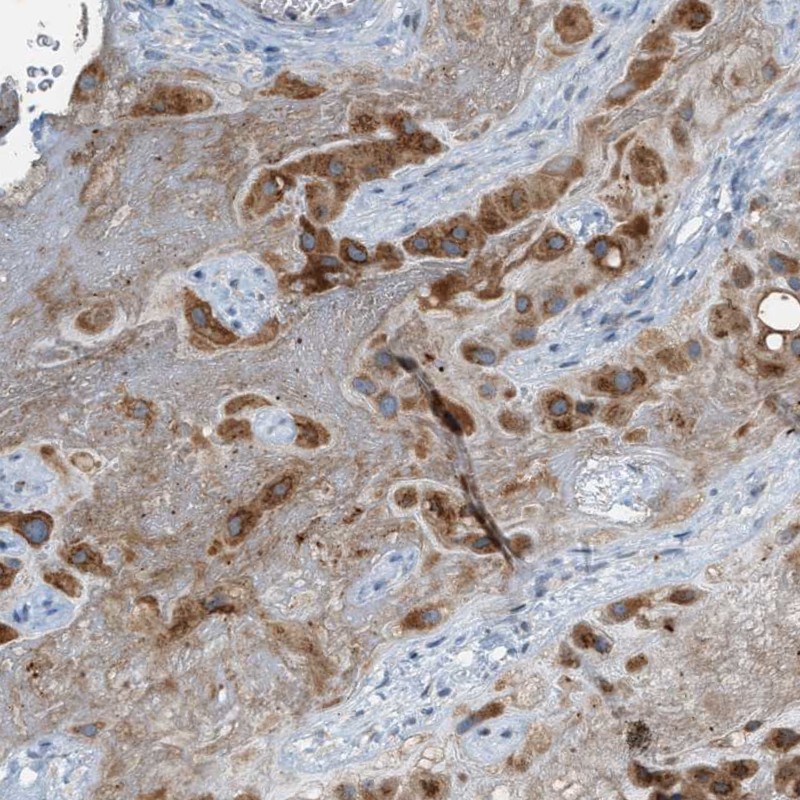

Immunohistochemical staining of human placenta shows strong cytoplasmic positivity in trophoblastic cells.